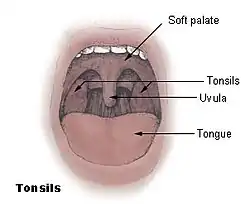

Soft palate

The soft palate (also known as the velum, palatal velum, or muscular palate) is, in mammals, the soft tissue constituting the back of the roof of the mouth. The soft palate is part of the palate of the mouth; the other part is the hard palate. The soft palate is distinguished from the hard palate at the front of the mouth in that it does not contain bone.

Upper respiratory system, with soft palate labeled near center. | |

Soft palate without tonsils (after tonsillectomy)

Soft palate without tonsils (after tonsillectomy) Sagittal section of nose mouth, pharynx, and larynx.